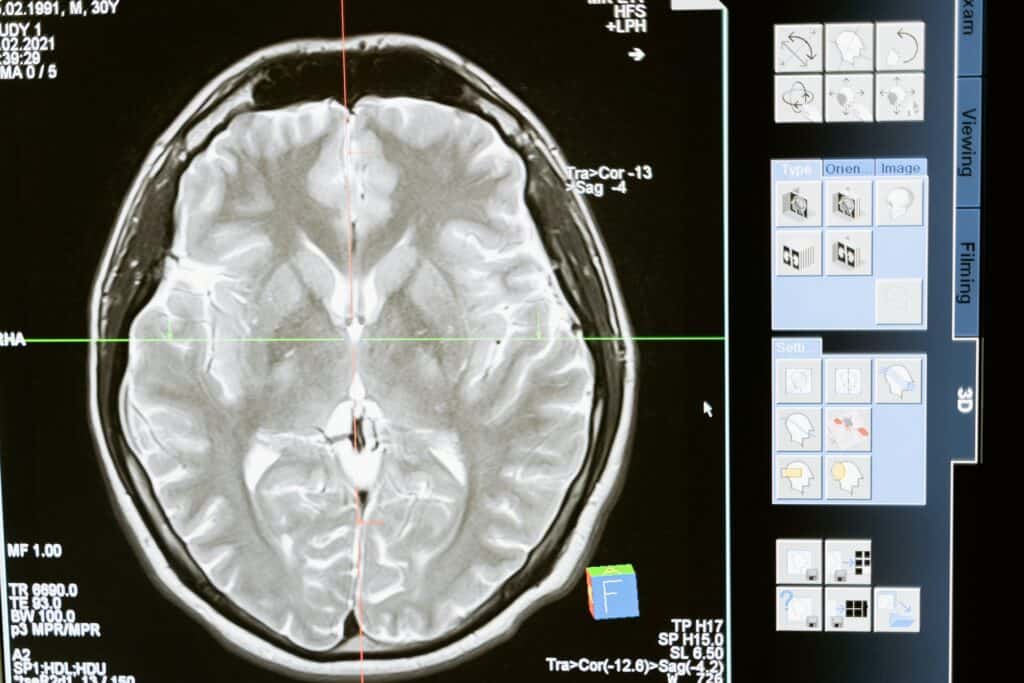

How to promote better mental health in the workplace

Mental health is a subject that’s long been misunderstood. As a society, we’ve tended to focus on the more severe examples of mental health problems: those that result in people being diagnosed with a condition and receiving professional help. The truth is, however, that mental health isn’t all too different from physical health in that […]